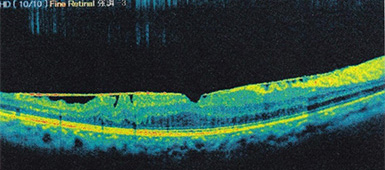

線状に見えるのが網膜前膜です。

手術前にあった線状のものが取り除かれています。